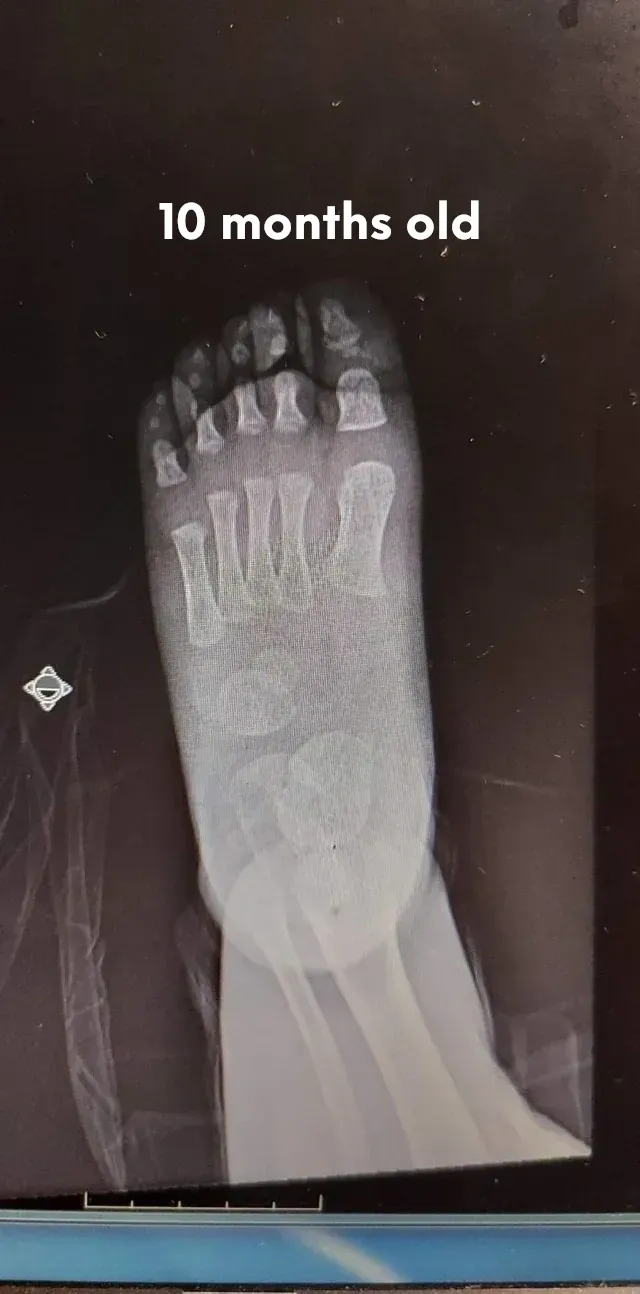

The pictures below will let you understand how babies' feet are developed. Here you can see how bones develop:

10 Months

18 YearsDear parents, children’s feet are developing structures, and the absence of an arch is a typical stage of development. Detailed X-RAY pictures above let us understand that babies' foot bones are not connected till the teen years. Only at the age of 14 may we consider that the bones in the feet have reached their connections. At the age of 18, we have fully completed foot structure, where muscles and bones create the whole support system.